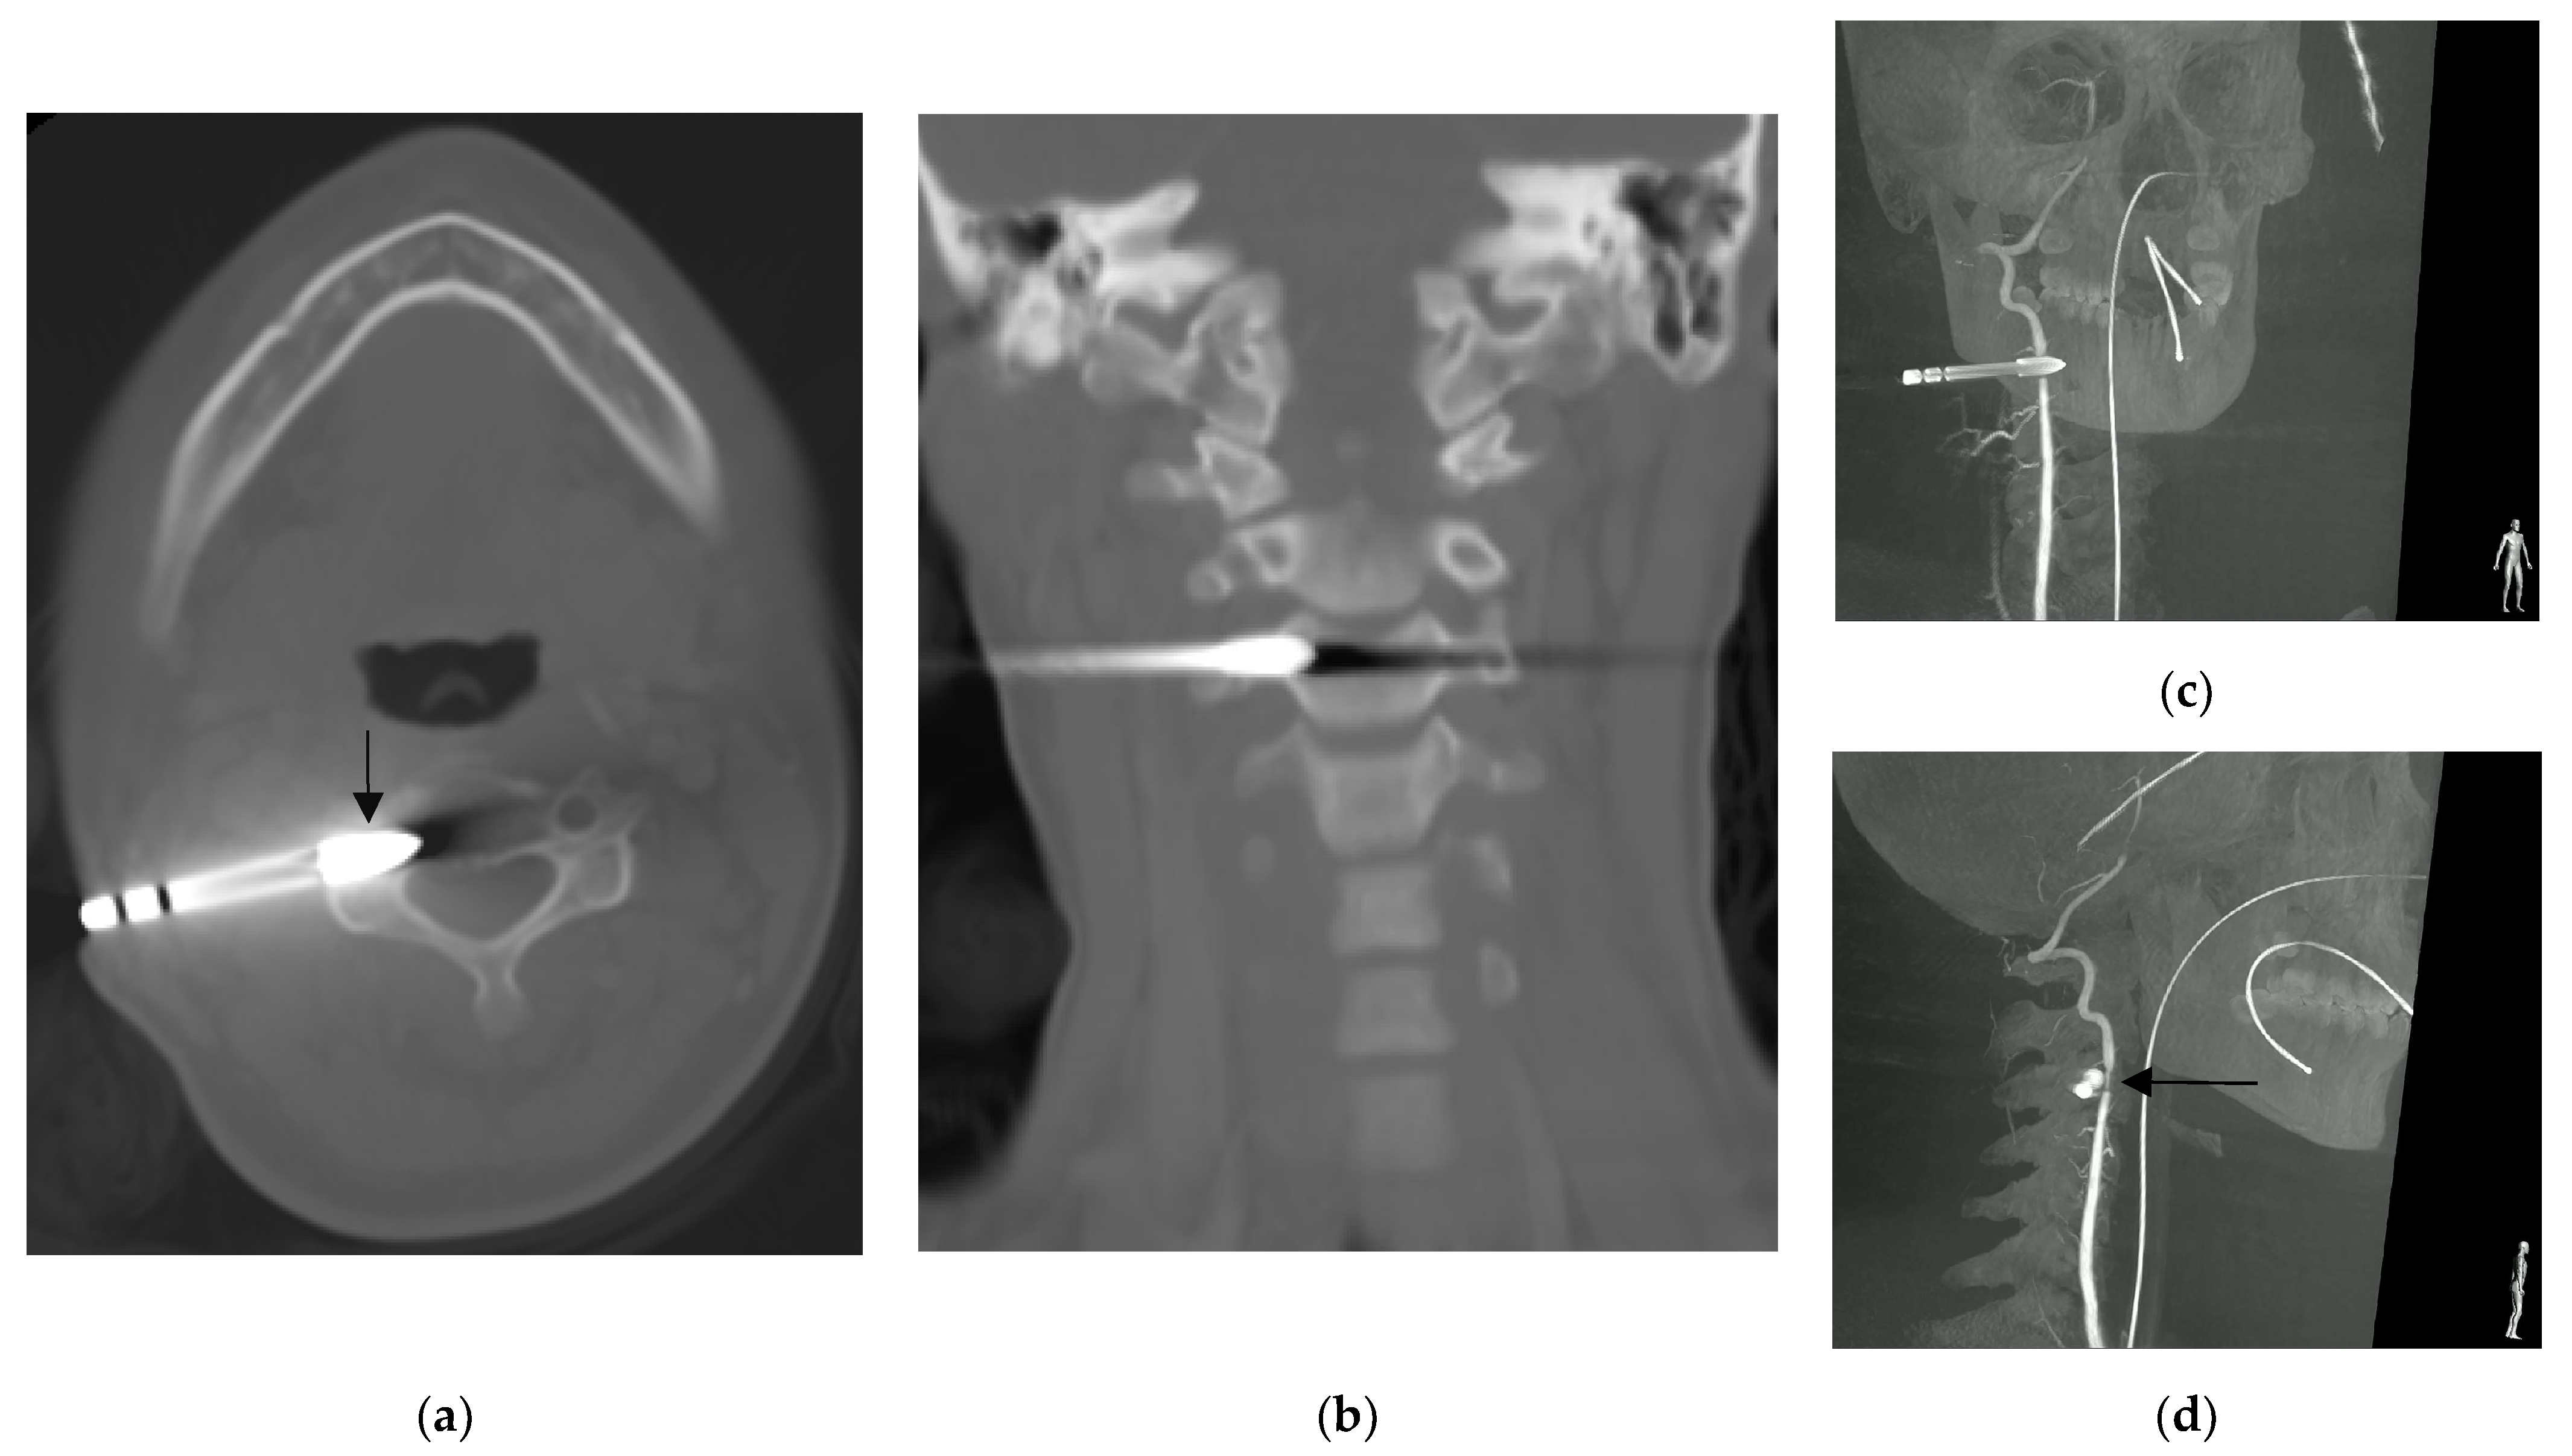

Computed tomography showing: (a) the arrowhead (arrow) lodged at the transverse foramen of third cervical vertebra without violating the central canal, and; (b) the coronal reconstruction of the same scan showed that the arrowhead did not violate the neural foramen. Right vertebral artery angiography rotation view (c,d) showed narrowing of the right vertebral artery indented by the arrowhead (arrow) [1].